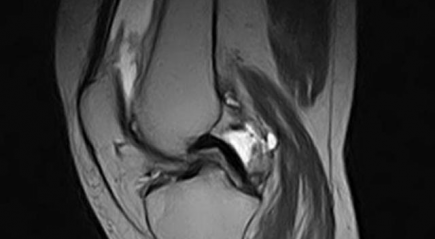

МРТ коленного сустава

МРТ коленного сустава позволяет получить максимально точную информацию при дегенерации и разрыве мениска, растяжении и разрыве связок, артрозе и артрите, подагре и новообразованиях в хрящах и костной ткани диафизов, а также определить необходимость артроскопии и выстроить ее схему.